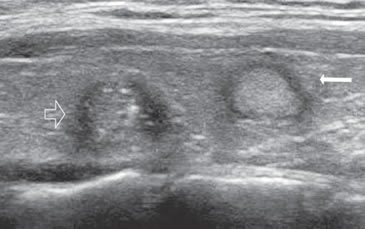

7. Invasión local y adenopatías

La extensión de la masa fuera de la cápsula, la infiltración de la tráquea o de los músculos pretiroideos es muy sugerente de malignidad (Figura 15a). Asímismo, la presencia de adenopatías con características típicas, debe hacer sospechar que el nódulo tiroideo es maligno. Los cánceres papilares de la tiroides son propensos a dar metástasis precozmente a los linfonodos cervicales y hasta la mitad de todos los pacientes pueden presentar adenopatías concomitantes. En 15% de los pacientes, el único signo de un cáncer tiroideo papilar oculto puede ser la detección de adenopatías. La mayoría de las metástasis ocurren ipsilateralmente al tumor primario en los grupos III y IV de la cadena yugular interna y del grupo VI del compartimiento central. En la ecografía, los linfonodos metastáticos pueden tener una forma redondeada o globular, una arquitectura con elementos sólidos o quísticos, con o sin microcalcificaciones y pérdida del hilio (Figura 15b y c). El “Doppler color” puede demostrar vasos capsulares de distribución caótica en reemplazo de los vasos hiliares normales (Figura 15d). Las adenopatías hiperecogénicas son sospechosas de cáncer papilar (Figura 16a). Los linfonodos normales en algunos grupos como el VI y el VII no se ven ecograficamente, de manera que si se hacen visibles, en el mismo lado del tumor, independiente del tamaño que tengan hay que considerarlos como adenopatías metastásicas (Figura 16b)

Figura 15. a) Cáncer papilar sólido de bordes lobulados (flechas) que muestra una gruesa calcificación central (flecha abierta) y múltiples

microcalcificaciones; b) Adenopatía cervical del grupo IV del mismo paciente (figura 15 a), hiperecogénica, con elementos quísticos (flecha

blanca) y microcalcificaciones agrupadas (flechas negras), típica de cáncer papilar; c) Adenopatías de grupo IV de un cáncer papilar, de

forma redondeada, hiperecogénicas, con pérdida del hilio, una anterior a la arteria carótida común (flecha) y otra lateral a la vena yugular

interna (flecha abierta); d) Corte sagital de la adenopatía lateral de la imagen 15 c), que en “doppler color” muestra vascularización patológica

y pérdida del hilio.

La apariencia ecográfica de los linfonodos metastásicos puede ser distinta a las del tumor primario y mostrar elementos quísticos y microcalcificaciones en mayor proporción que en el primario. En pacientes más jóvenes, las adenopatías puramente quísticas son relativamente comunes y cuando son solitarias pueden simular un quiste branquial o un quiste del conducto tirogloso.